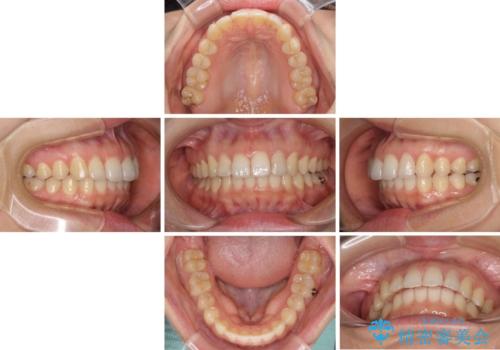

インビザライン矯正で前歯のデコボコを改善

- 前歯のデコボコを気にして来院された患者様です。

目立たないことを最優先にしたいとのことで、デコボコは軽度であったことから、インビザラインにて矯正治療を行うこととしました。

骨格的に下顎骨が左にずれており、上下の正中一致は困難ではありましたが、IPR(歯と歯の間を削る)や後方への移動など組み合わせて、できる限り改善しました。

インビザラインはマウスピースを外している時間が長いと、長期間使用しても前歯のデコボコはあまり改善されません。こちらの患者様は治療期間が長くなり、装着時間が短くなってしまったことで、気になる部分の改善により長期間を要するようになってしまいました。